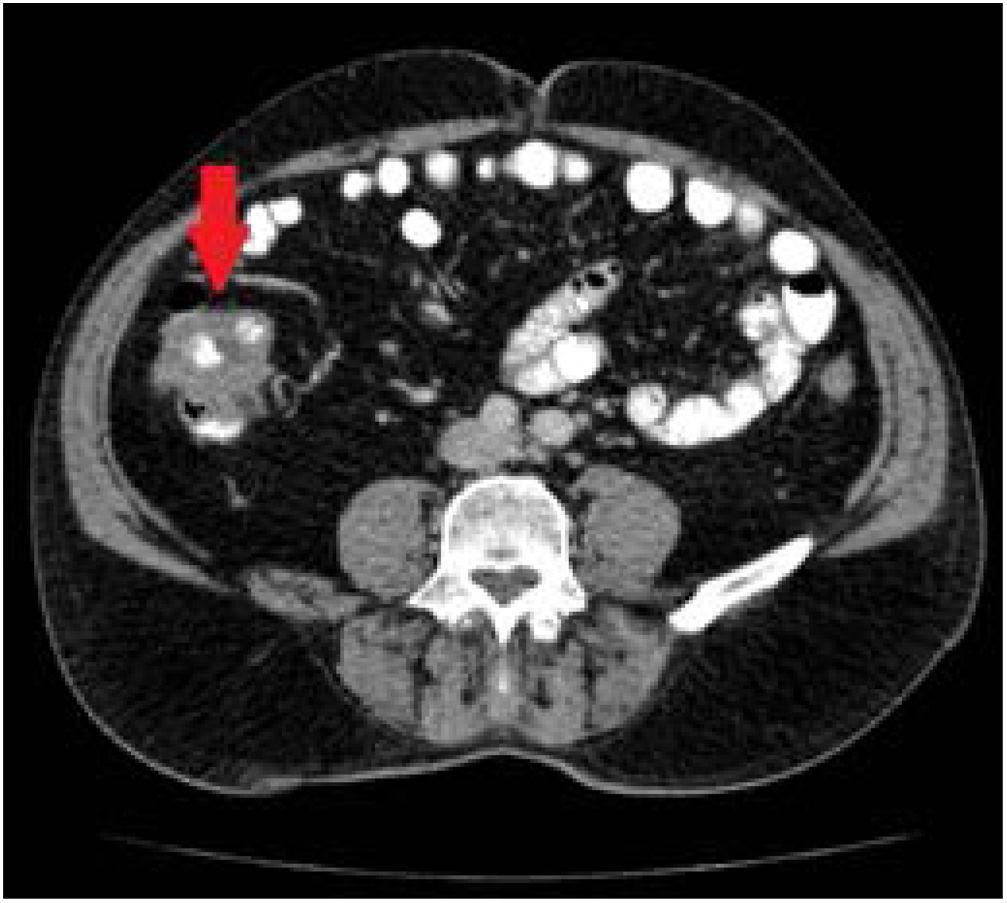

Abdominal tuberculosis is an ancient problem with modern nuances in diagnosis and management. The two major forms are tuberculous peritonitis and gastrointestinal tuberculosis (GITB), while the less frequent forms are esophageal, gastroduodenal, pancreatic, hepatic, gallbladder and biliary tuberculosis. The clinicians need to discriminate the disease Abdominal lymphadenopathy is the most common manifestation of abdominal TB, seen in 55–66% of patients, and may or may not be associated with other abdominal organ involvement.52 Abdominal lymph nodes are best evaluated on CT, which reveals enlarged nodes with hypoattenuating centres and hyperattenuating enhancing rims. 52, 53 On Abdominal ultrasound showed marked ascites and findings suggestive of peritoneal carcinomatosis. A CT of the abdomen revealed a

Abdominal lymphadenopathy is the most common manifestation of abdominal tuberculosis. Involvement of periportal, anterior pararenal,upper paraaortic and lesser omental lymph nodes. While tuberculosis (TB) is widely recognised as a respiratory disease, it can also affect other parts of the body, including the abdomen. Abdominal tuberculosis (ATB) is a form of extrapulmonary (outside the lungs) TB that impacts the gastrointestinal tract, peritoneum, abdominal lymph nodes, and sometimes the liver, spleen, and pancreas. Its clinical

Pombo et al. have described 4 types of contrast patterns on contrast-uptake CT of lymphadenopathy in individuals with abdominal tuberculosis: enhancement of the peripheral rim with a hypodense center, nonenhancing nodes, inhomogeneous and Abdominal tuberculosis is an increasingly common disease that poses diagnostic challenge, as the nonspecific features of the disease which may lead to diagnostic delays and development of complications. This condition is regarded as a great mimicker Abdominal tuberculosis continues to be endemic in the developing world and has shown a resurgence in the West. Computed tomography (CT) evaluation is singularly informative as it demonstrates involvement of the bowel, peritoneum, lymph nodes, and solid organs in a single examination. A spectrum of CT findings in an immunocompetent population is presented,